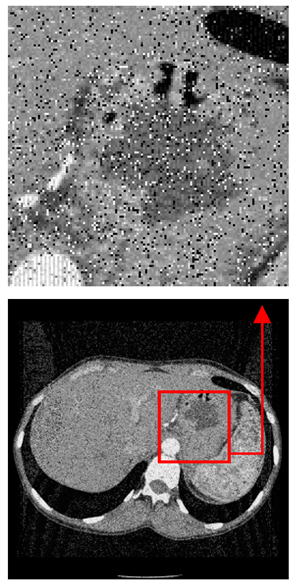

| Original Medical Images | Shadow Images Produced by Using (7,4) Hamming Code (MSBs) | ||

|---|---|---|---|

| Pair 1 | Pair 2 | ||

![]() | ![]() | ![]() | ![]() |

| Pair 3 | Pair 4 | ||

| Shadow images produced by using (15,11) Hamming code (LSBs) | Shadow images produced by using (15,11) Hamming code (MSBs) | ||